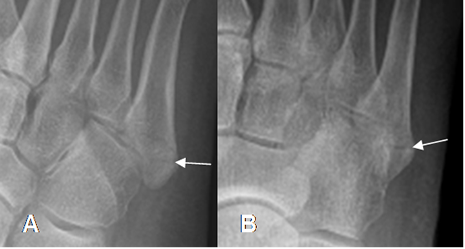

Del 5º metatarsiano: Ocurre en su base y es producida por una inversión forzada. Causa avulsión sobre la inserción de la aponeurosis plantar o del peroneo breve. (10).

(Fig 52 A y B).

Fig 52 A. Avulsión del 5º metatarsiano.

A: Rx oblicua y B: Rx AP. Fractura no desplazada en la base del 5º metatarsiano, por avulsión no desplazada.

Fig 52 B. Avulsión del 5º metatarsiano.

A: Rx AP y B: RX oblicua. Fractura desplazada y con compromiso intra-articular, en la base del 5º metatarsiano, por avulsión desplazada.